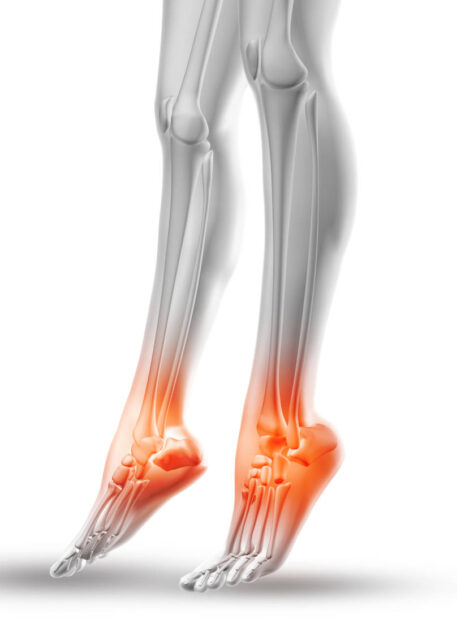

Artroza (artritis) zgornjega skočnega sklepa je degenerativna sprememba, ki povzroči obrabo hrustanca med golenico, mečnico in skočnico (talus). Pojavlja se pri starejših, a tudi pri mlajših po travmatskih poškodbah, kot so zvini, zlomi ali izpahi.

Funkcija sklepa: Omogoča dorzalno fleksijo (dvig stopala proti sebi) in plantarno fleksijo (potisk stopala navzdol – “špička”).

01. Najpogostejši simptomi

- Bolečina v predelu sklepne linije zgornjega skočnega sklepa

- Omejena gibljivost (težava pri dvigu ali spustu stopala)

- Tog občutek v gležnju po mirovanju

- Otekanje sklepa